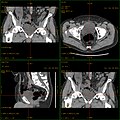

Craniale Computertomographie Abgebildet sind Felsenbein und Nasennebenhöhlen. Aufgrund der hohen Auflösung der Aufnahme des verwendeten 64-Zeilen-CTs sind selbst die Gehörknöchelchen erkennbar. -

Koronal reformatierte Darstellung von Abdomen und Becken; gut zu erkennen sind u. a. die Leber und die beiden Nieren. -

Kombination aus multiplanarer Reformatierung und sliding thin slab. Der Bildkursor befindet sich in der Harnblase. Die Originalschichtdicke beträgt 1,25 mm, dargestellt wird in allen Ansichten gemittelt (= average) in 3,7 mm bzw. 3,8 mm Dicke. -